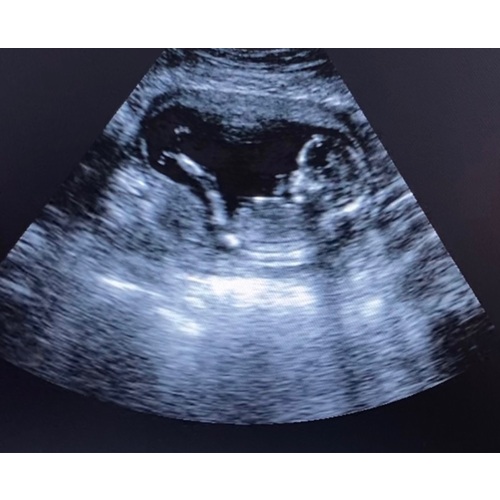

Doordat het lage stralingen zijn kun je hiermee niet het geslacht zien. Misschien wel bij 30 weken? Maar op de site staat dat je dat hiermee niet kunt zien. Op een gegeven moment was de baby aan het koprollen, maar niks kunnen zien. Of het komt omdat het misschien een meisje is 😋😅